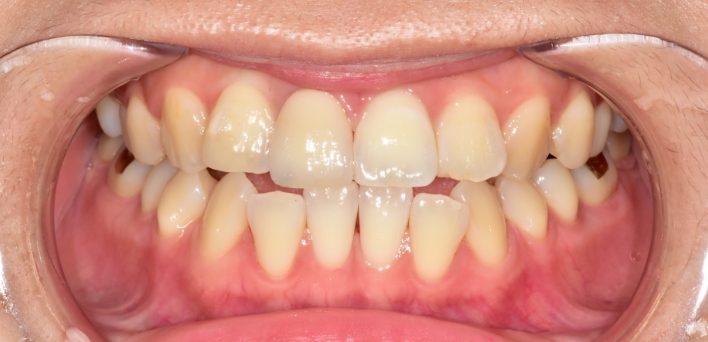

단순하게 예쁘고, 심미적으로 만드는 인위적인 작업물이 아닌,

자연치아와 가장 유사하도록 치아를 복구하는데에 초점을 맞추어

치아복구 + 치아성형 2가지의 장점을 합쳐

개개인 손상 정도에 따른 맞춤형 보철을 제작합니다.

그저 예쁘기만한 부자연스러운 라미네이트가 아닙니다.

더서울치과의원은 각 개인의 얼굴 특성에 맞는 맞춤형 라미네이트를 선물합니다.